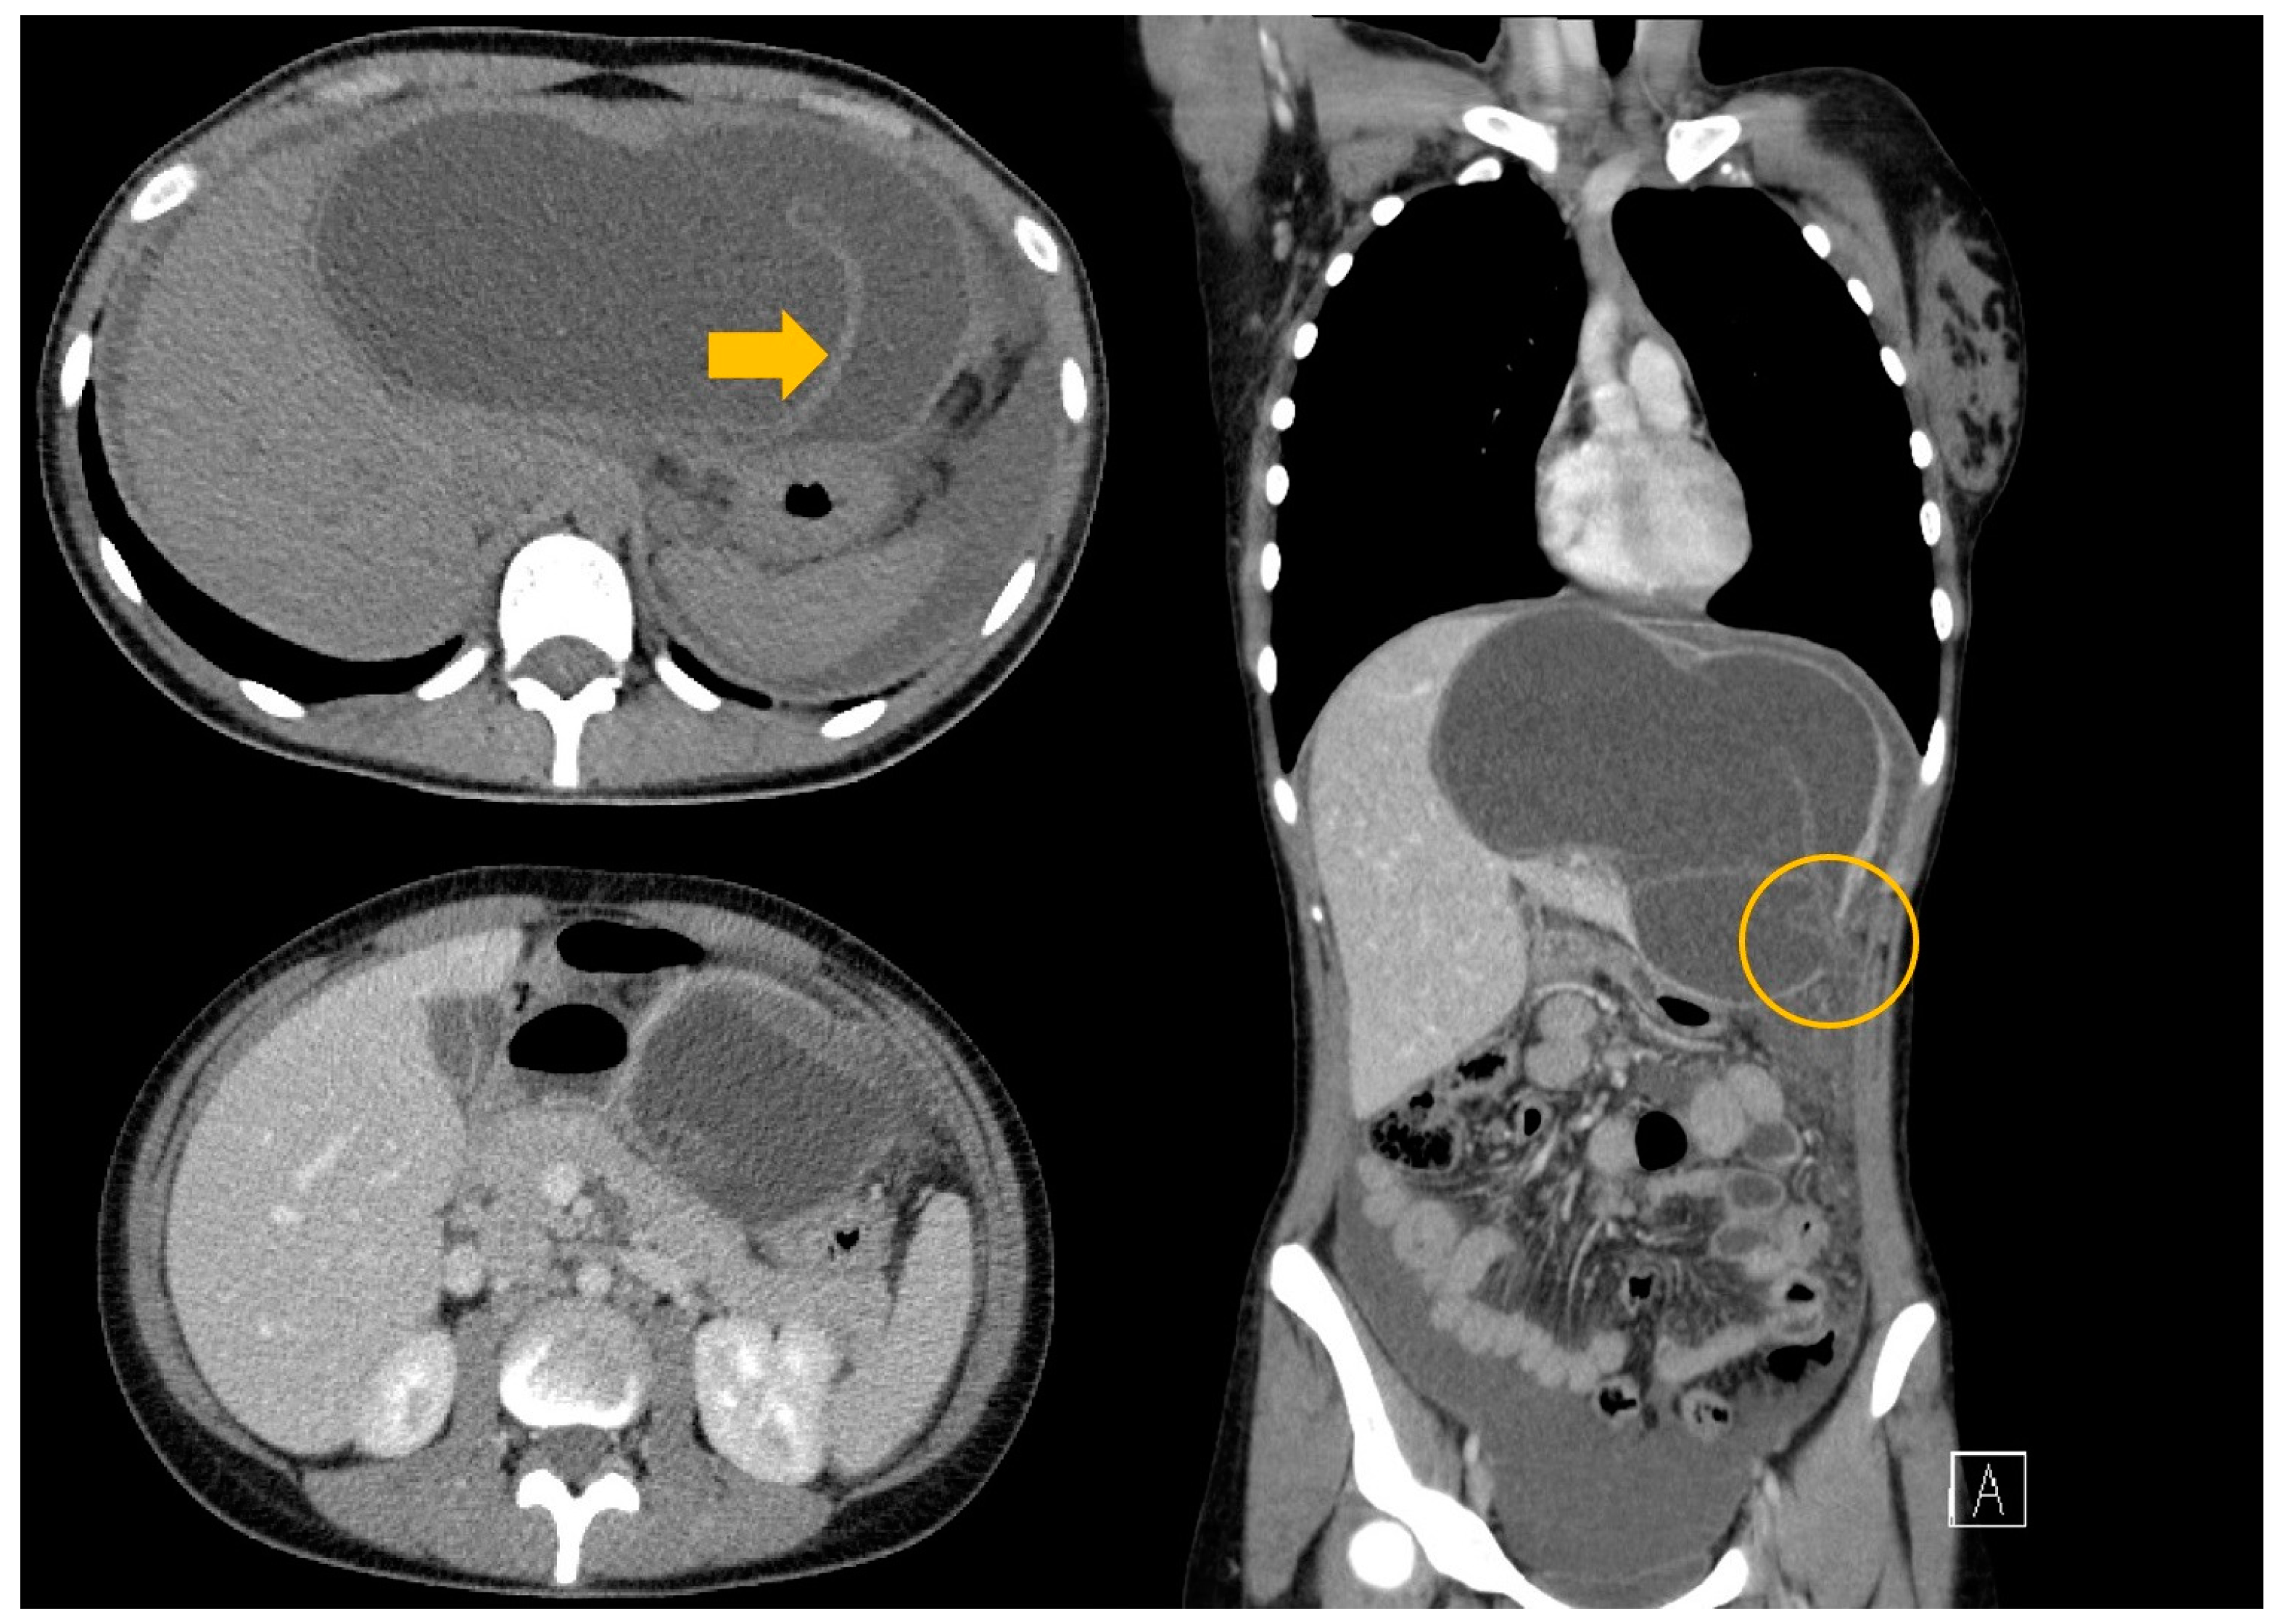

3.1. Case 1

3.2. Case 2